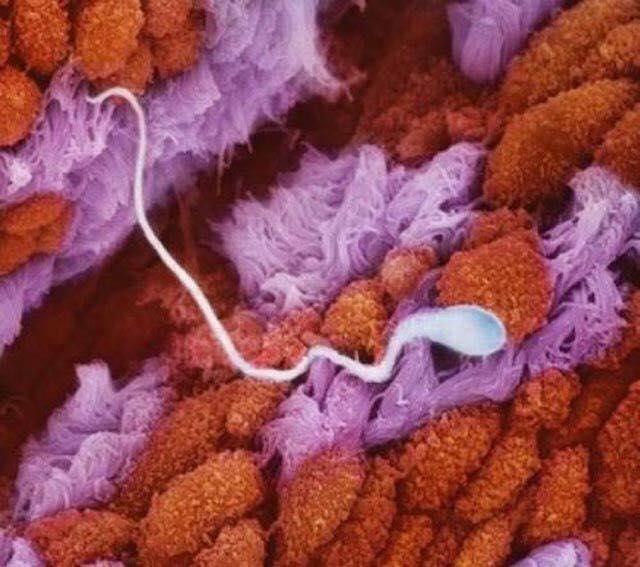

Esperma nas tubas uterinas

Tubas uterinas